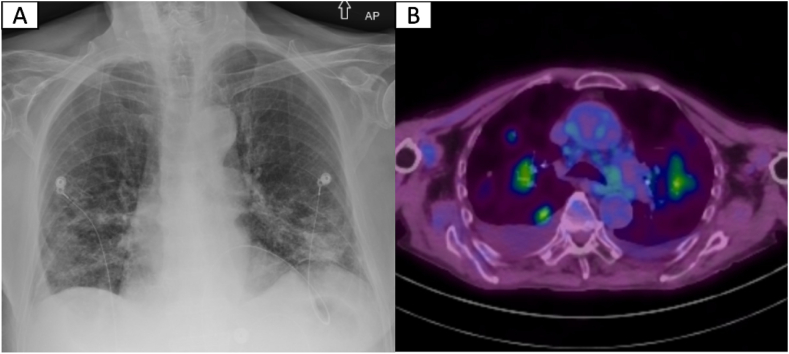

An 89-year-old male with a medical history of non-ischemic cardiomyopathy was initially admitted with acute hypoxic respiratory failure attributed to heart failure exacerbation. Aside from progressive dyspnea, a non-pruritic, non-painful rash and constitutional symptoms were reported. Initial work-up was remarkable for normocytic anemia, lymphopenia, mild hypercalcemia, and elevated inflammatory markers. Despite aggressive diuresis, his respiratory distress worsened requiring up-titration of supplemental oxygen (6–8L/min). Subsequent chest CT showed diffuse, ill-defined areas of consolidation and ground-glass opacities (GGOs) with areas of solid and ground-glass nodularity. Rheumatologic work-up was remarkable for mildly elevated ANA titer of 1:60, and positive anti-centromere antibody of 1.8 AI (normal range 0–0.9 AI). Infectious work-up was negative. Due to high oxygen requirements, tissue sampling was obtained by skin biopsy instead of bronchoscopy. After biopsy testing, prednisone 60 mg was started with posterior clinical and radiographic improvement. Biopsy results revealed cutaneous MZL. Follow-up PET scan showed persistent but improved diffuse GGOs and nodular opacities. Given the clinical presentation, imaging and skin biopsy results, the diagnosis was compatible with EMZL with synchronous pulmonary and skin manifestations. Empiric treatment with Rituximab and steroid taper was planned. At 6-month follow-up, the patient reported clinical and respiratory improvement.